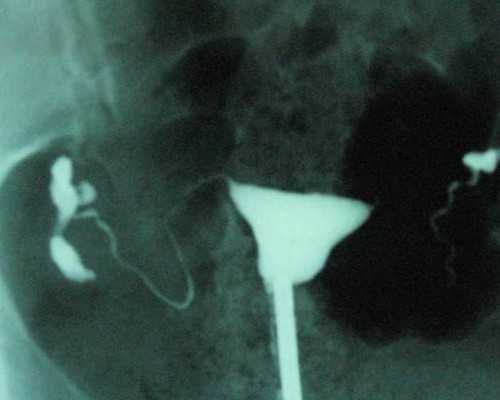

(3)采集卵子:于卵泡发育成熟尚未破裂时,在腹腔镜下经腹或在B超监视下,经阴道以针穿刺成熟卵泡,抽取卵泡内容物,找出卵母细胞。

(5)体外授精:将在无菌条件下取得的丈夫精液,经过处理,使精子具备穿入卵子的能力,成为授精小滴,然后加入含有卵子的培养基内。通过二性原核融合形成一个新细胞即受精卵,然后继续培养。得其分裂至8~16 个细胞时,将胚泡以导管注入宫底部,最好一次能够移植 3~4个受精卵,可提高移植后妊娠的成功率。胚泡移植成功取决于受精卵本身的生命力,子宫内膜是否健康,以及移植过程有无损伤。